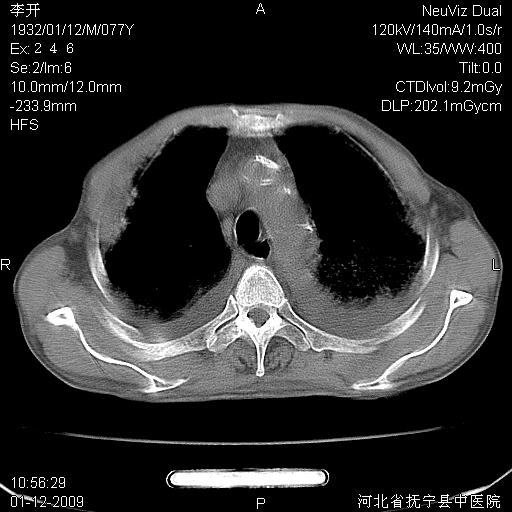

以下是引用黑白光影在2009-1-19 16:49:00的发言:[br]心衰肺水肿;心包、胸腔积液;冠脉钙化;肺部感染。